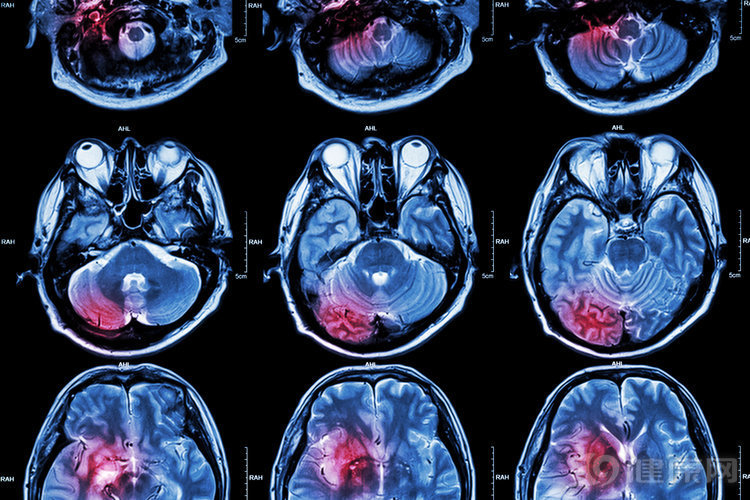

人到中年 , 发生脑梗的几率会大大增加 , 在我们身边都经常能听到脑梗发生的病例 。 即使“捡回”一条命 , 发生脑梗之后 , 很多患者会留下严重的后遗症 , 因此一定要重视 。

脑梗又被称之为脑卒中 , 是一种急性脑血管疾病 , 具有发病率高、死亡率高以及致残率高的特点 , 给全社会以及各个家庭都带来了非常沉重的负担 。 冬春交替时节正是脑梗的高发期 , 因为现在气温依然较低 , 人所处的环境温差比较大 , 这样一来血压就很难保持稳定 , 再加上血流动力也会发生改变 , 从而导致脑卒中发病率大大增加 。

而脑卒中主要分为两种类型 , 一种是和脑血管破裂相关的出血性脑卒中 , 占发病总人数的三四成;而另外一种则是血管狭窄以及血流阻断引起的缺血性脑卒中 , 这类人群占到总人数的6.7成 。

不论是出血性脑卒中还是缺血性脑卒中 , 都会给患者的身体带来巨大威胁 , 我国每年新发病例已经由200万增加至370万 。